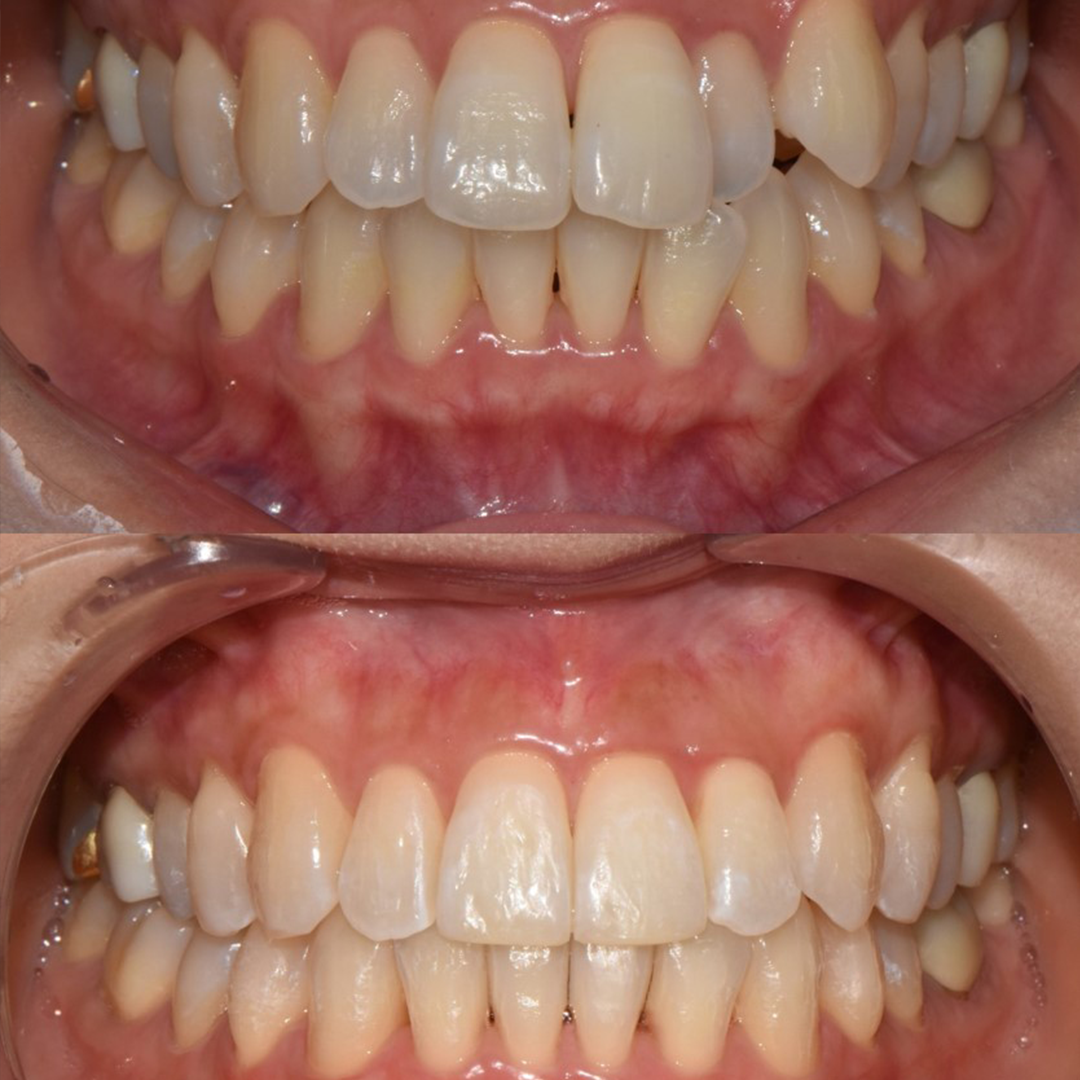

전체 임플란트

상·하악 전체 치아를 대체하는 임플란트로 최소한의 식립을 통해

자연치아와 비슷한 기능을 수행할 수 있도록 합니다.